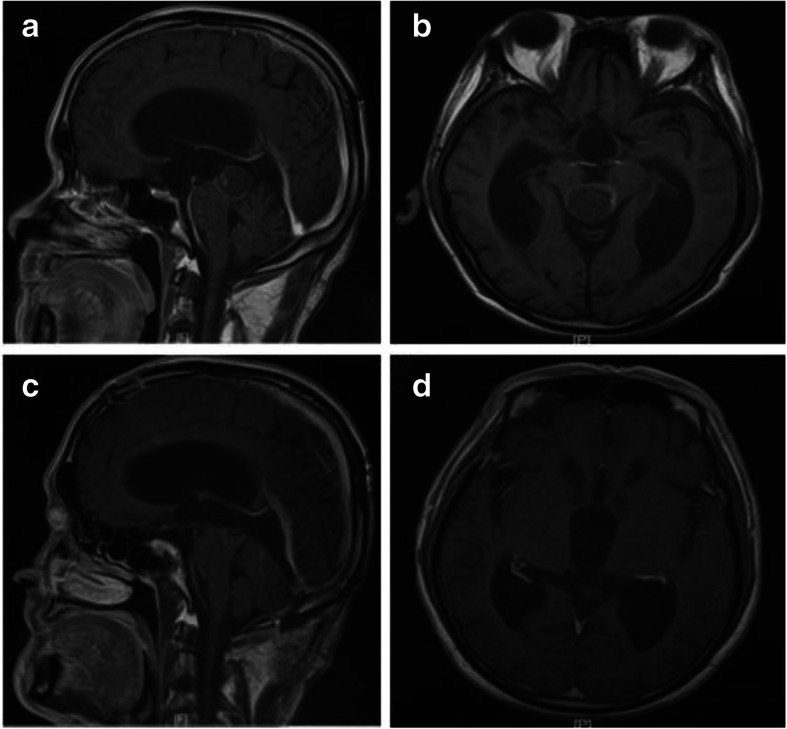

Fig. 4.

Preoperative and postoperative images of germinoma: a and b preoperative MRI shows tumor in the pineal region; c and d Three days after subtotal resection of the tumor; e and f Three months after operation, the tumor disappeared after radiotherapy and chemotherapy

Preoperative and postoperative images of cavernous hemangioma: a and b preoperative MRI shows tumor in the pineal region; c and d One month after total resection of the tumor